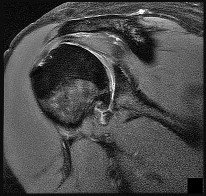

Figure 26 is the MR image of a 55-year-old man who sustained an acute traumatic injury to his right shoulder and loss of active range of motion. He was initially evaluated by his primary care physician and treated with physical therapy without success. He was referred to an orthopaedist for surgical consultation 8 weeks after sustaining the injury. The orthopaedic surgeon performs a successful arthroscopic repair but notes poor tendon quality at the repair site. The treating surgeon keeps the patient in a sling full time for 6 weeks without formal therapy. One year after surgery, in comparison to early therapy, this rehabilitation program will likely result in

Historically, orthopaedic surgeons considered early range-of-motion programs following rotator cuff surgery secondary to concerns about potential postsurgical stiffness. Although this may have been a primary open repair concern, arthroscopic surgery appears to substantially decrease this risk. More recently, investigators are reporting similar results in terms of range of motion, retear rate, and functional outcome scores among patients who undergo early and delayed rehabilitation programs.